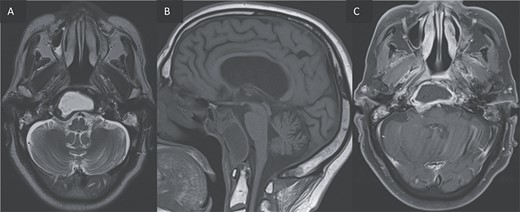

For better diagnostic assessment, the patient underwent a magnetic resonance imaging (MRI) (Figs 3 and 4), it showed the following findings:

An expansile cystic-necrotic lesion localized in the central region of the clivus, characterized by a hypointense rim on T2-weighted images.

Post-gadolinium T1-weighted imaging delineating the cystic center with thick peripheral rim enhancement.

Diffusion-weighted imaging (DWI) and apparent diffusion coefficient (ADC) maps demonstrating central restricted diffusion.

Furthermore, inflammatory changes were noted to extend into the petrous, tympanic, and mastoid segments of the right temporal bone, as well as involving the petrous and mastoid regions of the left temporal bone and the occipital bone. Additionally, small abscess cavities were observed within the right occipital condyle.

(A, B) Axial T2 and sagittal T1 images showing an expansile cystic lesion in the center of the clivus hyperintense in T2, hypointense in T1, with a rim hypointense in T2-weighted image. (C) Post-gadolinium T1-weighted shows a peripheral rim enhancement of the clival lesion.